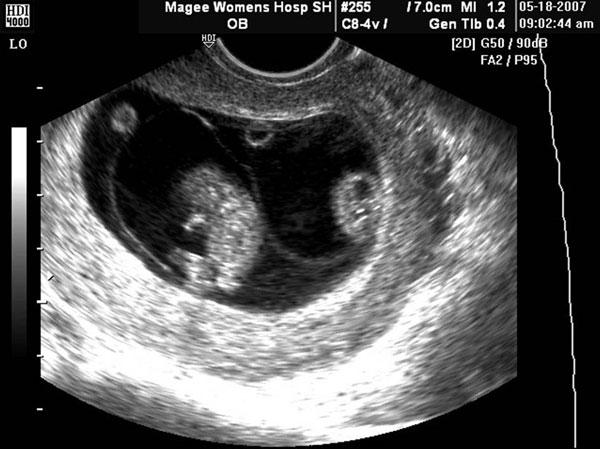

Dấu Lamda trong song thai 2 bánh nhau và dấu chữ T trong song thai 1 bánh nhau.

Dấu hiệu màng ối dày 3 mm, có nhiều lớp trong song thai hai bánh nhau và màng ối mỏng 1.4 mm, không thấy rõ các lớp trong song thai 1 bánh nhau